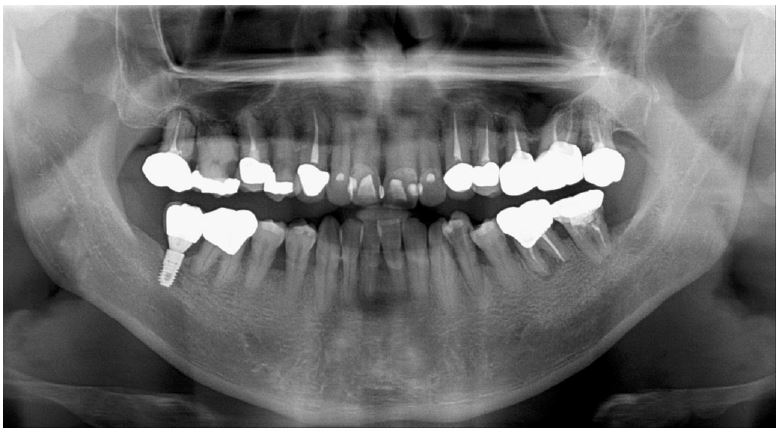

Clinical examination revealed bleeding on probing with a 7 mm PD of the buccal furcation of the maxillary right first molar (#16). Radiographic examination confirmed apically involved alveolar bone loss in the buccal roots of the mandibular first molars. (Fig. 7). It was assumed that initial stability could be achieved in the apical and septal bones, and extraction and iARP were planned. The patient was instructed to rinse with 0.12% chlorhexidine digluconate solution for 2 minutes for oral disinfection. The tooth was extracted using luxators and extraction forceps under local anesthesia with 2% lidocaine containing 1:80,000 epinephrine (Fig. 8A, 8B). After debridement of granulation tissues and irrigation with a sterile normal saline solution, immediate implant placement at the septal bone (TS III 5.0 × 8.5 mm; OSSTEM) was performed (Fig. 8C). The ISQ value at 1st surgery was 60. The gap between the implant surface and the extraction socket wall was filled with DBBM and covered with NBCM in a double-layer fashion (Fig. 8D). Thereafter, the hidden X suture and horizontal mattress suture were placed over NBCM without primary wound closure (Fig. 8E, 8F). Fourteen days after surgery, the patient returned for suture removal and postoperative examination. A delayed healing pattern with yellowish granulation tissue above the extraction socket was observed, and a depressed healing pattern of soft tissue with exposure to the cover screw was observed even after four weeks (Fig. 8G, 8H).

Fig. 8.

Case 2: Clinical photographs of the immediate implant placement with alveolar ridge preservation. (A) Initial clinical photograph of the maxillary right first molar, (B) Buccal gingival tears observed after tooth extraction, (C) Immediate implant placement in the septal bone, (D) Deproteinized bovine bone mineral was placed in the extraction socket, (E) Hidden X and horizontal mattress sutures are placed over the native bilayer collagen membrane, (F) Panoramic radiograph after implant placement, (G) Delayed gingival healing with yellowish granulation tissue observed at stitch out (2 weeks), (H) Cover screw exposure with depressed gingival healing was observed during a recall check (4 weeks).